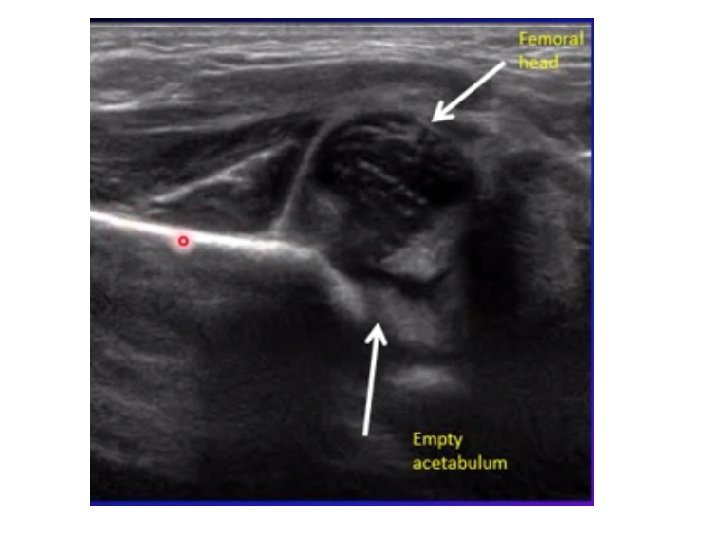

Developmental dysplasia of the hip (DDH) • Developmental dysplasia (abnormal development) of the hip refers to a variety of conditions where the femoral head and the acetabulum are improperly aligned. Previously known as congenital dislocation. Occur as a result of abnormal development of the hips during fetal development, more in female than male. • These conditions include dislocation (displacement of the bone from its normal position in a joint), subluxation (partial dislocation), and acetabular dysplasia.

• How to assess : • a. Positive Barlows test: ( Ortolan’s sign) click heard on abduction of thighs. • b. Shorting of limb on the affected side. • c. Asymmetrical thigh and gluteal folds. • d. Restriction of abduction. • e. After walking begins waddling gait in (bilateral) or limping in (unilateral).